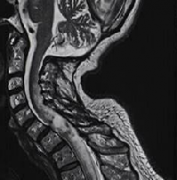

脊髓肿瘤 约占中枢神经系统肿瘤的15%,大多数硬膜内肿瘤起源于脊髓和终丝、神经根或脑膜的细胞成分。脊柱硬膜内腔的转移很少表现为肿块病变。硬膜内脊髓肿瘤是根据其与脊髓的关...

脊髓肿瘤 ,也称椎管内肿瘤(intraspinal tumors),是发生于脊髓本身及椎管内与脊髓邻近组织(脊神经根、硬脊膜、脂肪组织、血管、先天性残留组织等)的原发性肿瘤或转移性肿瘤的总...